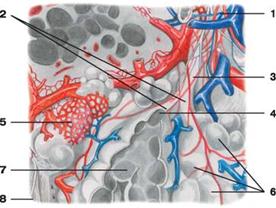

Ацинусы (грозди) являются структурно-функциональными единицами легкого, которые осуществляют основную функцию легких - газообмен. В каждую легочную дольку входят 16-18 ацинусов. Ацинус начинается от концевой бронхиолы, которая дихотомически делится на дыхательные бронхиолы 1-2-3 порядка и переходит в альвеолярные ходы и альвеолярные мешочки с расположенными на их стенках альвеолами легких. Число легочных ацинусов в одном легком достигает 150000. В каждый ацинус входит большое количество альвеол.

1 — бронхиола;

2 — альвеолярные ходы;

3 — дыхательная (респираторная) бронхиола

4 — предсердие;

5 — капиллярная сеть альвеол;

6 — альвеолы легких;

7 — альвеолы в разрезе; 8 — плевра

Рис. Долька легкого:

Альвеолы - это выпячивания в виде пузырьков диаметром до 0.25 мм, внутренняя поверхность которых выстлана однослойным плоским эпителием, расположенным на сети эластических волокон и оплетенным снаружи кровеносными капиллярами. Альвеолы покрыты изнутри тонкой пленкой фосфолипида - сурфактантом, который понижает поверхностное натяжение и препятствует слипанию альвеол при выдохе. Толщина стенки альвеолы в местах соприкосновения (прилежания) безъядерных участков эпителиоцитов легких и эндотелия капилляров составляет около 0.5 мкм. На свободной поверхности эпителиоцитов имеются очень короткие цитоплазматические выросты, обращенные в полость альвеол, что увеличивает общую площадь соприкосновения воздуха с поверхностью эпителия. Общее количество альвеол в обоих легких у взрослого достигает от 600 до 700 млн, а общая дыхательная поверхность всех альвеол составляет около 100кв.м.